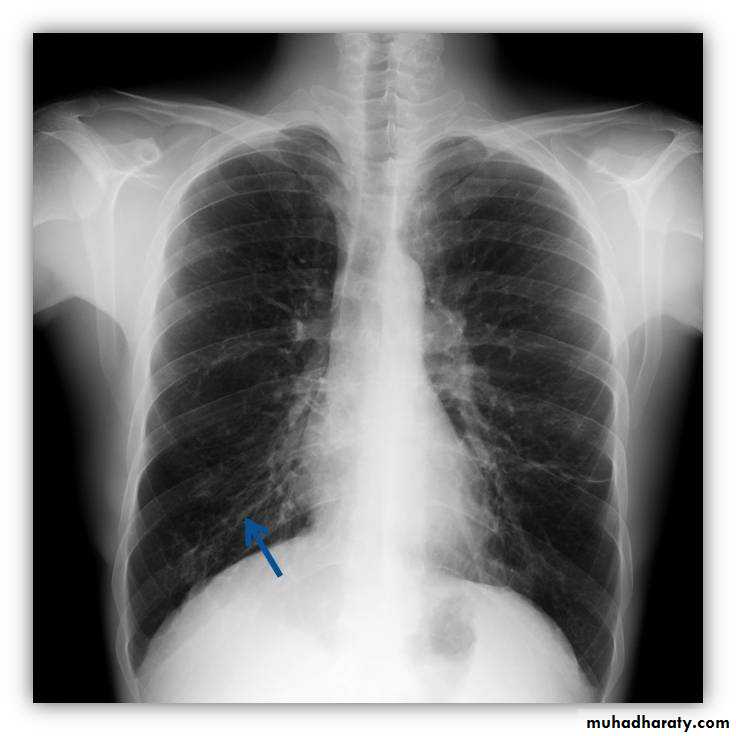

Nipple shadow